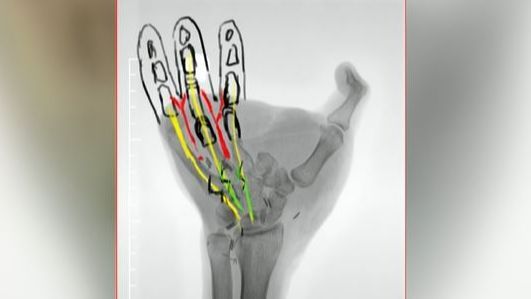

Según el doctor, el joven tendrá "tres dedos y el pulgar". Diego ha podido ver cómo será el implante gracias a una radiografía. Lo más "complicado" de este proceso quirúrgico, apunta Francisco del Piñal, es "conectar las arterias y las venas".